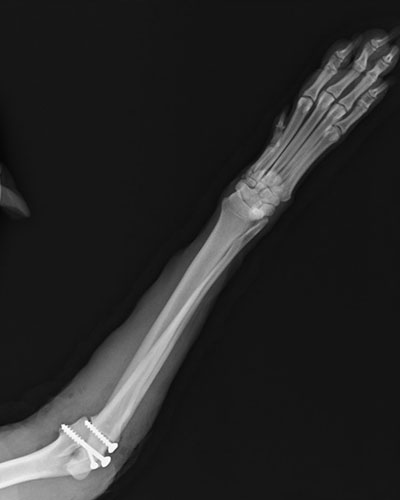

左前肢橈尺骨骨折

一個跳躍後左前肢突然不敢採地的壯壯,經X光確認為左前肢橈尺骨骨折,手術完美復位,目前已可正常行走。

術後